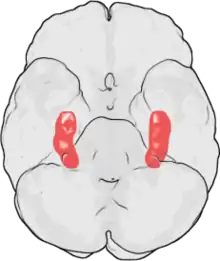

![]() يقع قرن آمون في الفص الصدغي الوسطي للدماغ. في هذه النظرة الجانبية للدماغ يظهر الفص الجبهي إلى اليسار وفص مؤخر الرأس إلى اليمين بينما الفصان الجداري والصدغي تم إزالتهما بشكل كبير لإظهار مكان قرن آمون في الأسفل مباشرة. | |